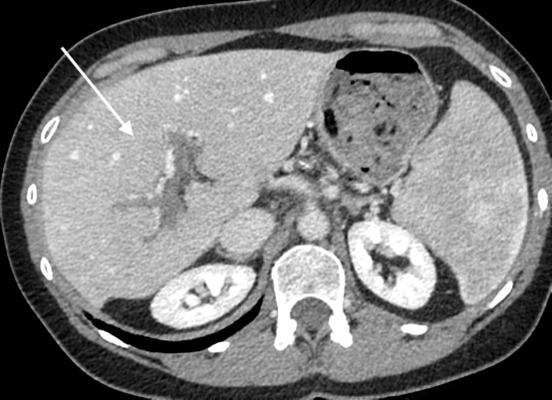

Dysmorphie hépatique

Classiquement, la dysmorphie cirrhotique associe une atrophie du foie droit et du segment IV, une hypertrophie du lobe gauche et du segment I, et des contours bosselés. En cas de maladie vasculaire, la dysmorphie est différente et il est important de comprendre que les zones qui s’atrophient sont celles qui souffrent le plus. Ainsi  :

• en cas de thrombose porte segmentaire ou lobaire, la zone concernée s’atrophie progressivement  ;

• en cas de maladie vasculaire présinusoïdale (par exemple MVPS ou thrombose porte), on observe volontiers une atrophie du foie périphérique, un segment IV de taille normale ou augmentée, des contours lisses du foie (fig. 2)  ;

• en cas de maladie vasculaire post-sinusoïdale (par exemple syndrome de Budd-Chiari), la dysmorphie est plus variable, dépendant des atteintes veineuses. Le segment I est très hypertrophié dans plus de 50  % des cas.